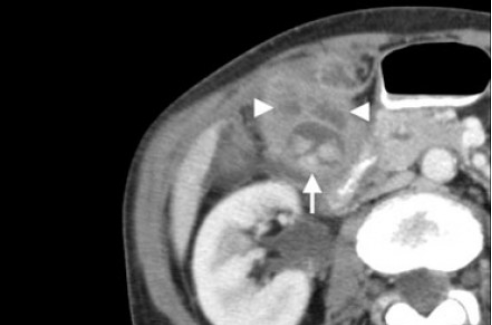

(Левый) На поперечном УЗ срезе у пациента с эмфиземой и перфорацией желчного пузыря определяется разрыв стенки, отмечается исчезновение эхогенной полосы слизистой. В просвете желчного пузыря определяются газ и скопление перипузырной жидкости.

(Правый) При КТ с контрастным усилением на аксиальной томограмме у этого же пациента наблюдаются признаки острого эмфизематозного холецистита с перфорацией. Виден фокальный разрыв стенки желчного пузыря. Также определяется газ в просвете пузыря и в перипузырном пространстве.